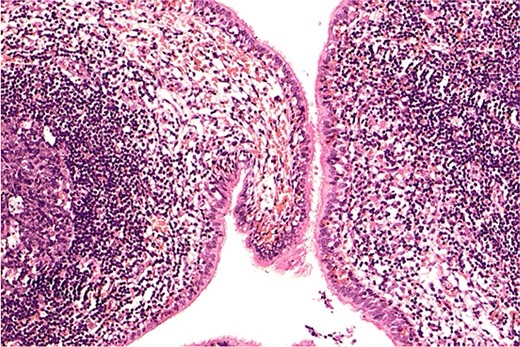

Postoperatively, the patient began oral intake after 6 hours. On postoperative Day 1, the vital signs of the patient stabilized, and cardiac monitoring was discontinued. A complete blood count indicated elevated white blood cells (WBC count 23.67 × 109/L); however, the body temperature was normal. The patient received intravenous cefuroxime sodium 1.5 g every 12 hours for infection and oral ambroxol for mucus clearance. Coagulation tests indicated a D-dimer level of 9.84 μg/ml, prompting the administration of subcutaneous enoxaparin 4000 U once daily to prevent deep vein thrombosis. The patient began ambulation on postoperative Day 1 under multimodal analgesia. On postoperative Day 2, a fever developed, peaking at 38.1°C with a heart rate of 104 bpm. The patient reported a cough with yellowish sputum. Despite 3 days of cefuroxime sodium treatment, the patient continued to have a fever (37.8°C) and purulent sputum. Therefore, on postoperative Day 4, the antibiotic regimen was switched to intravenous piperacillin–tazobactam 4.5 g every 12 hours. By Day 5, the body temperature normalized. After three days on piperacillin–tazobactam, a repeat complete blood count showed a significant reduction in WBC count (8.89 × 109/L), and antibiotics were discontinued. A chest X-ray on postoperative Day 4 confirmed effective re-expansion of the right lung. Daily drainage volumes were 50–190 ml. The chest drainage tube was removed on postoperative Day 7. Cultures from the intraoperative pus and postoperative sputum did not yield any pathogens, with only normal flora being identified. Pathological examination of the excised right middle lobe confirmed a bronchogenic cyst (Fig. 3). The patient was discharged on Day 9 post-surgery.